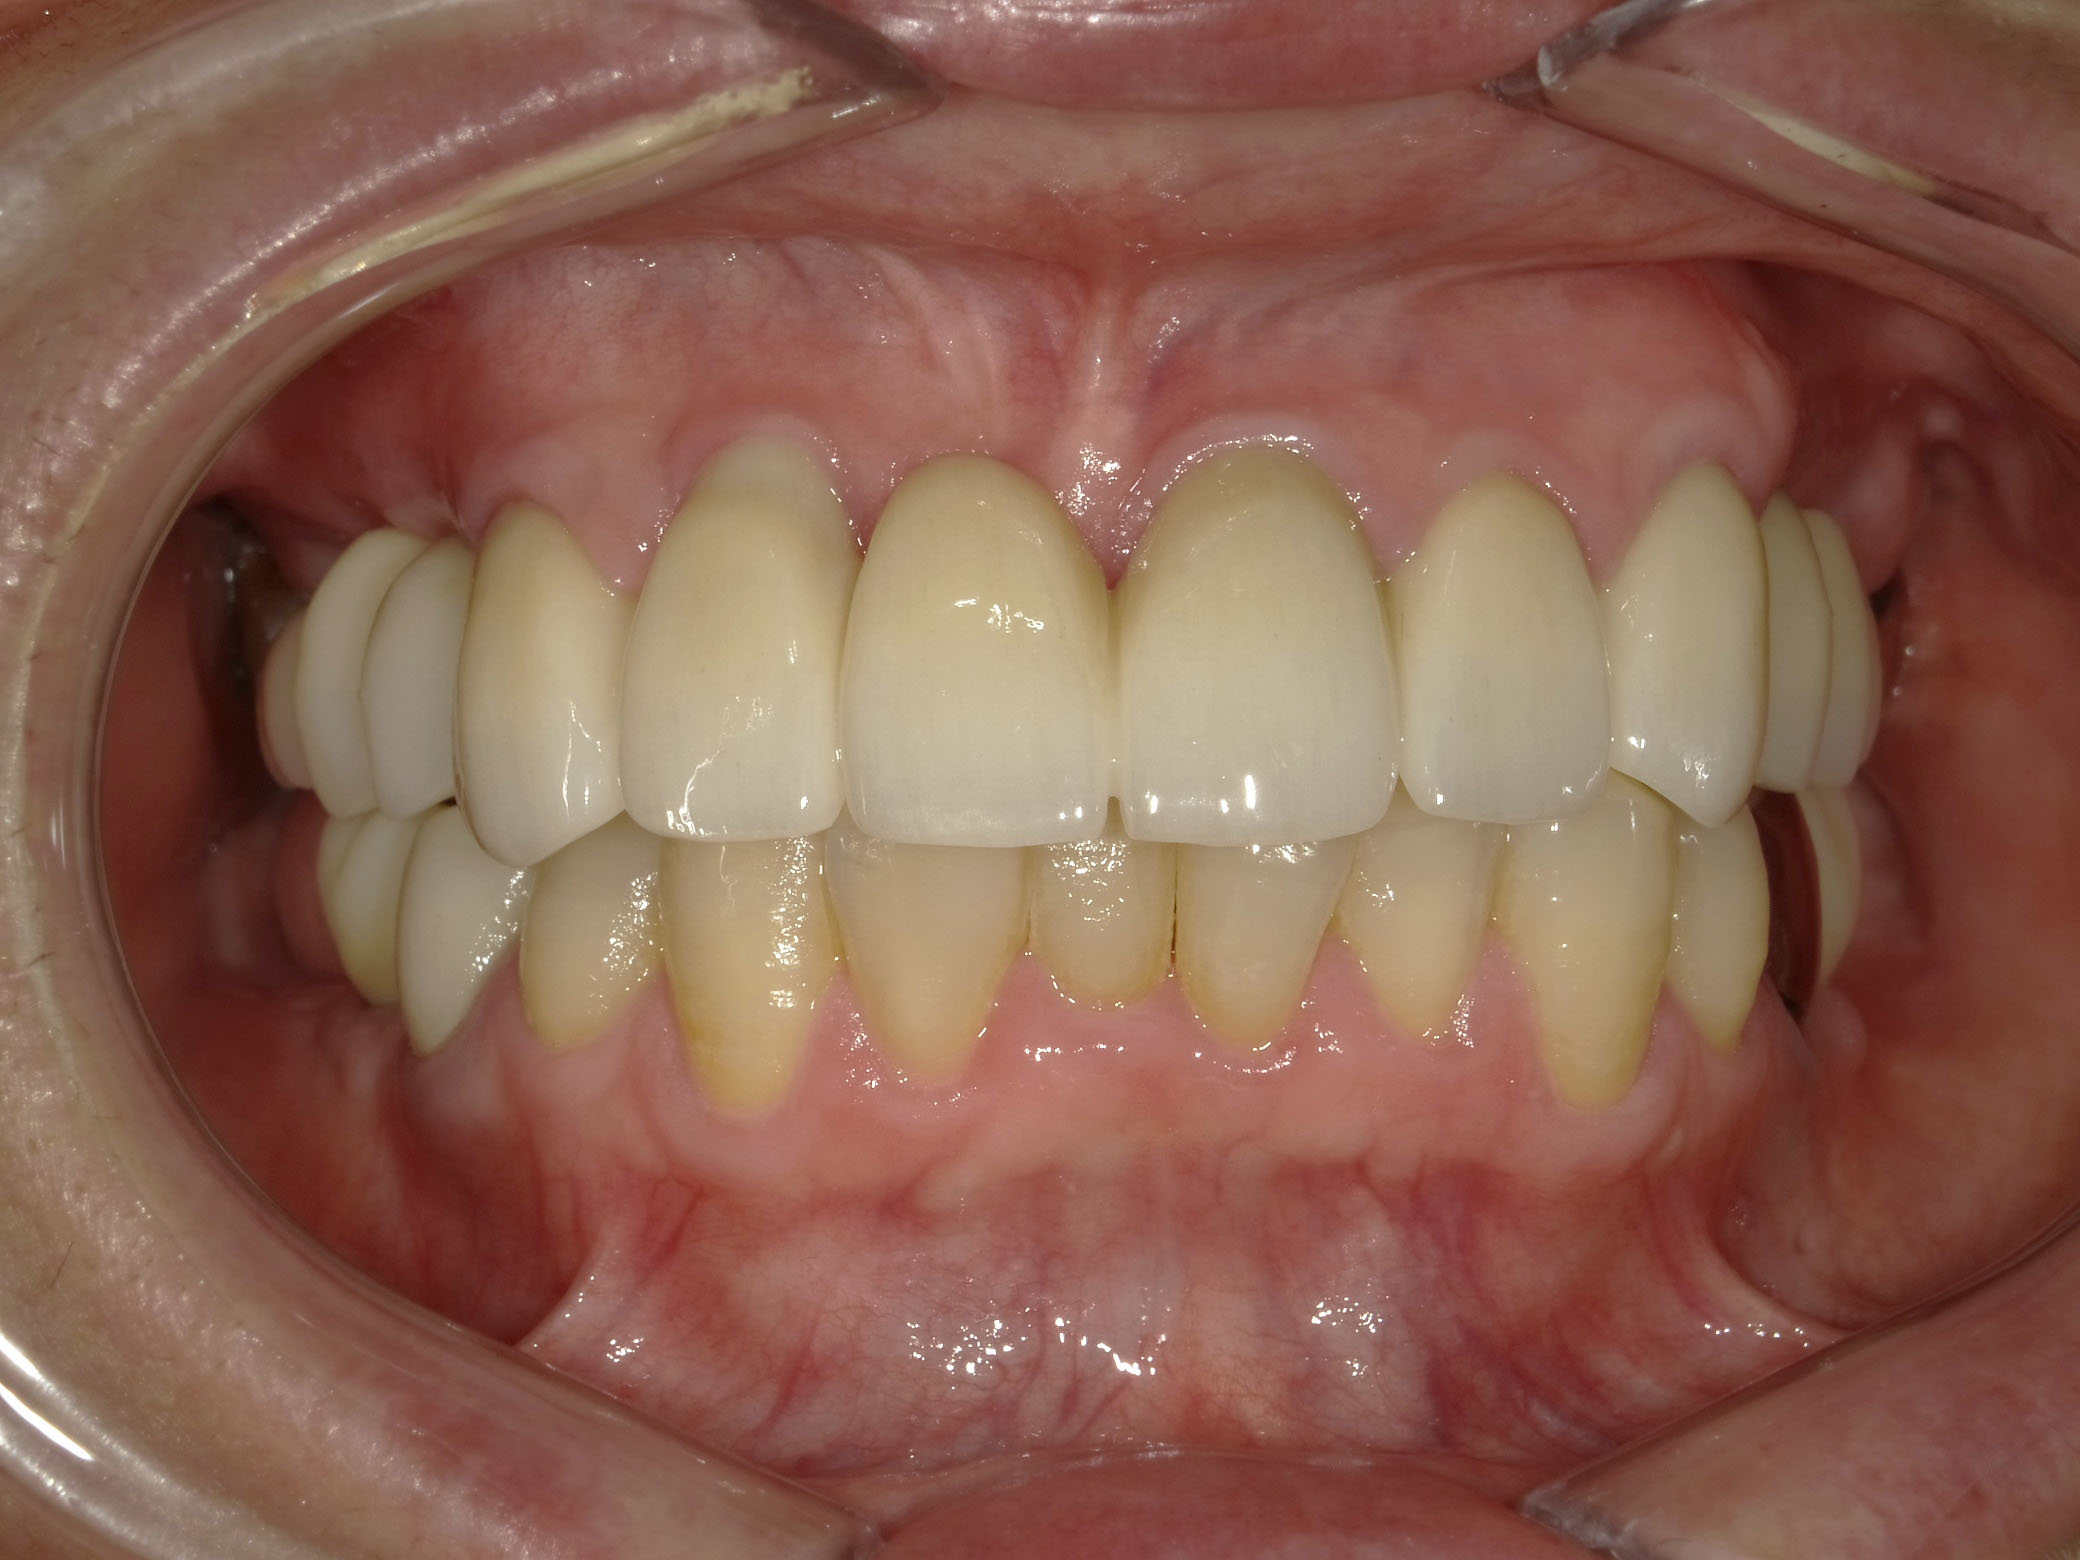

BEFORE

AFTER

主訴

全体的に見た目を綺麗にしたい。奥歯でしっかり噛みたい。

診断名・主な症状

臼歯部欠損

年齢

70歳

治療内容

インプラント埋入(右上4・6,左上4・6,右下6,左下6)

ジルコニアBr(右上3―左上3)

ジルコニア(右下5,左下5)

治療期間/

通院回数

インプラント 1年5ヶ月/13回

ジルコニアBr、ジルコニアクラウン 3ヶ月/10回

費用

インプラント: 2,552,000円

その他治療: 640,000円

合計 3,192,000円

*いずれも税込